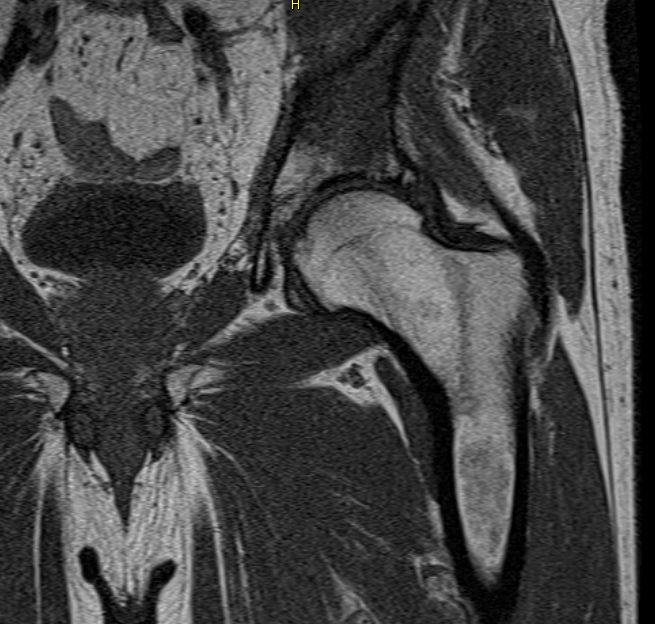

| MRT | Knochenmetastasen im MRT: linkes Pfannendach, Kreuzbein.![]() |